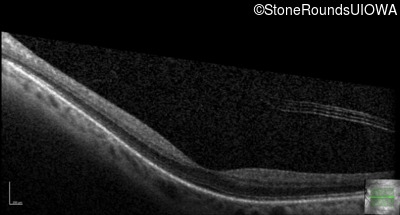

Optical Coherence Tomography - Left - 20/25 +2

Exemplar / OCT Stack